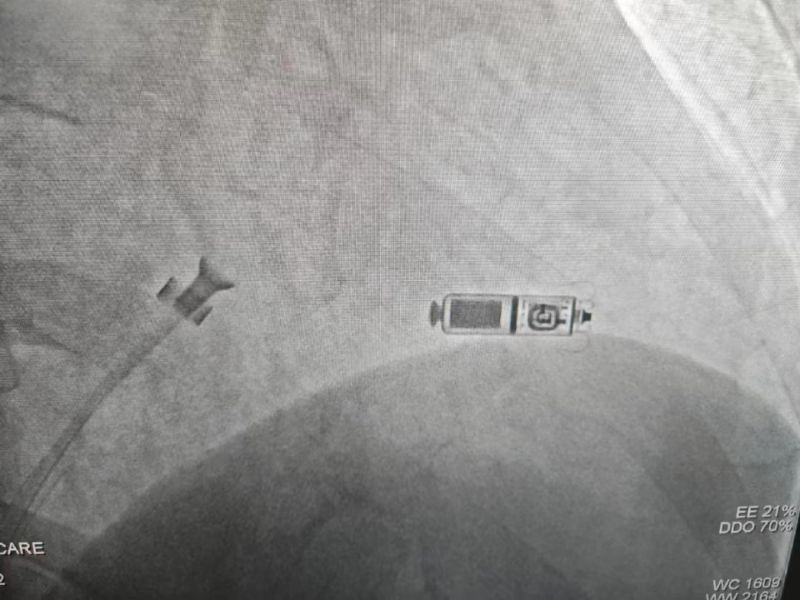

國慶前夕,延安大學(xué)咸陽醫(yī)院心血管內(nèi)科五病區(qū)成功完成了一例Micra雙腔無導(dǎo)線起搏器的植入術(shù),這是延安大學(xué)咸陽醫(yī)院在實(shí)施首例單腔無導(dǎo)線起搏器后,再次完成首例雙腔無導(dǎo)線起搏器(Micra)的植入手術(shù),也是咸陽市首例雙腔無導(dǎo)線起搏器植入術(shù)。此次接受Micra無導(dǎo)線起搏器是延安大學(xué)咸陽醫(yī)院心血管內(nèi)科五病區(qū)患者何大爺(化名),患者15天前出現(xiàn)心悸、氣短,伴短暫性意識障礙,當(dāng)?shù)蒯t(yī)院診斷“急性腦梗死”,因錯過最佳溶栓及取栓時(shí)機(jī),患者出現(xiàn)左側(cè)肢體無力來我院神經(jīng)內(nèi)科就診,于住院第二天,患者再次突發(fā)意識障礙,心電監(jiān)護(hù)最長停搏5秒以上,搶救治療后出現(xiàn)快速型心房顫動及心房撲動,因患者有心臟停搏,發(fā)作心動過速時(shí)應(yīng)用抗心律失常藥物風(fēng)險(xiǎn)太高,給治療造成巨大困難,這嚴(yán)重威脅著患者的進(jìn)一步診療。

經(jīng)心血管病院李陽主任、何克強(qiáng)主治醫(yī)師等仔細(xì)分析病情,充分觀察并排除藥物等影響因素后,最終確定患者為病態(tài)竇房結(jié)綜合征(慢快綜合征),考慮到患者血栓風(fēng)險(xiǎn)較高,傳統(tǒng)起搏器為減少術(shù)中及術(shù)后切口處出血,需停用抗凝藥,該患者停用抗凝藥物會增加患者再發(fā)腦梗死或者腦梗進(jìn)展的風(fēng)險(xiǎn),其次患者后期仍需復(fù)查頭顱MR明確腦梗死恢復(fù)情況,與患者及家屬溝通后選擇安裝無需停用抗凝藥物及術(shù)后可行核磁共振檢查的雙腔無導(dǎo)線永久起搏器。

手術(shù)過程:經(jīng)過充分的術(shù)前討論,在延安大學(xué)咸陽醫(yī)院心血管病院吳棟梁院長、劉雄濤副院長的指導(dǎo)與支持下,李陽教授、何克強(qiáng)主治醫(yī)師、辛浩主治醫(yī)師與導(dǎo)管室介入團(tuán)隊(duì)的共同努力下,經(jīng)過超聲科、心電中心等多學(xué)科協(xié)作,成功為患者植入雙腔無導(dǎo)線永久起搏器,術(shù)后第二天患者在起搏器保障下經(jīng)藥物治療恢復(fù)正常的竇性心律。目前患者心臟情況及腦梗均恢復(fù)良好,已順利出院。

科普:Micra無導(dǎo)線起搏器號稱“世界最小起搏器”,無需植入心內(nèi)膜導(dǎo)線,也無需在胸前皮下制作囊袋放置脈沖發(fā)生器(起搏器),手術(shù)僅需局部麻醉,通過股靜脈穿刺,將起搏器經(jīng)導(dǎo)管植入心腔內(nèi),手術(shù)時(shí)間短,減少出血、血腫及感染風(fēng)險(xiǎn),術(shù)后恢復(fù)快,肢體活動不受限,無異物感。

優(yōu)勢:比傳統(tǒng)起搏器體積減少93%,體積更小,重量僅2g,類似一顆維生素膠囊;雖體積只有傳統(tǒng)起搏器十分之一,但其小小身體儲存大能量,續(xù)航時(shí)間超過12年,整個手術(shù)過程平均約30分鐘,植入成功率高,術(shù)后8-12小時(shí)即可下床活動,術(shù)后1-2天即可出院;兼容1.5T(特斯拉)/3.0T全身核磁共振掃描。滿足患者植入Micra之后疾病的診斷和治療需求。